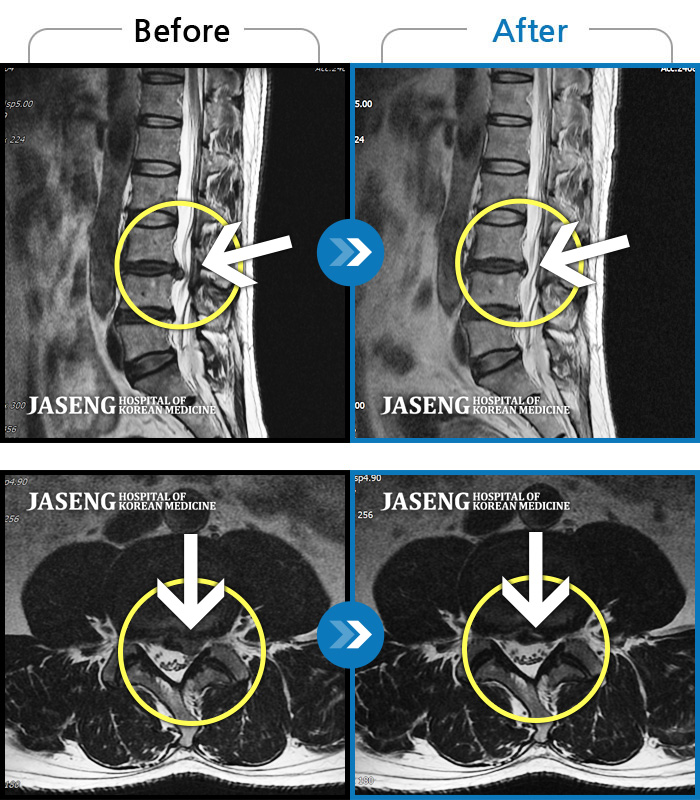

수술을 해야 하는 상황이었는데 자생 한방 병원의 김유진 원장님 덕분에 현재 수술없이 잘 치료를 받고 있습니다.

처음에 수술없이 완쾌할수 있을까 걱정을 많이 했지만 지금은 완쾌할수 있을거랑 희망을 가지고 통원치료를 받고 있습니다.